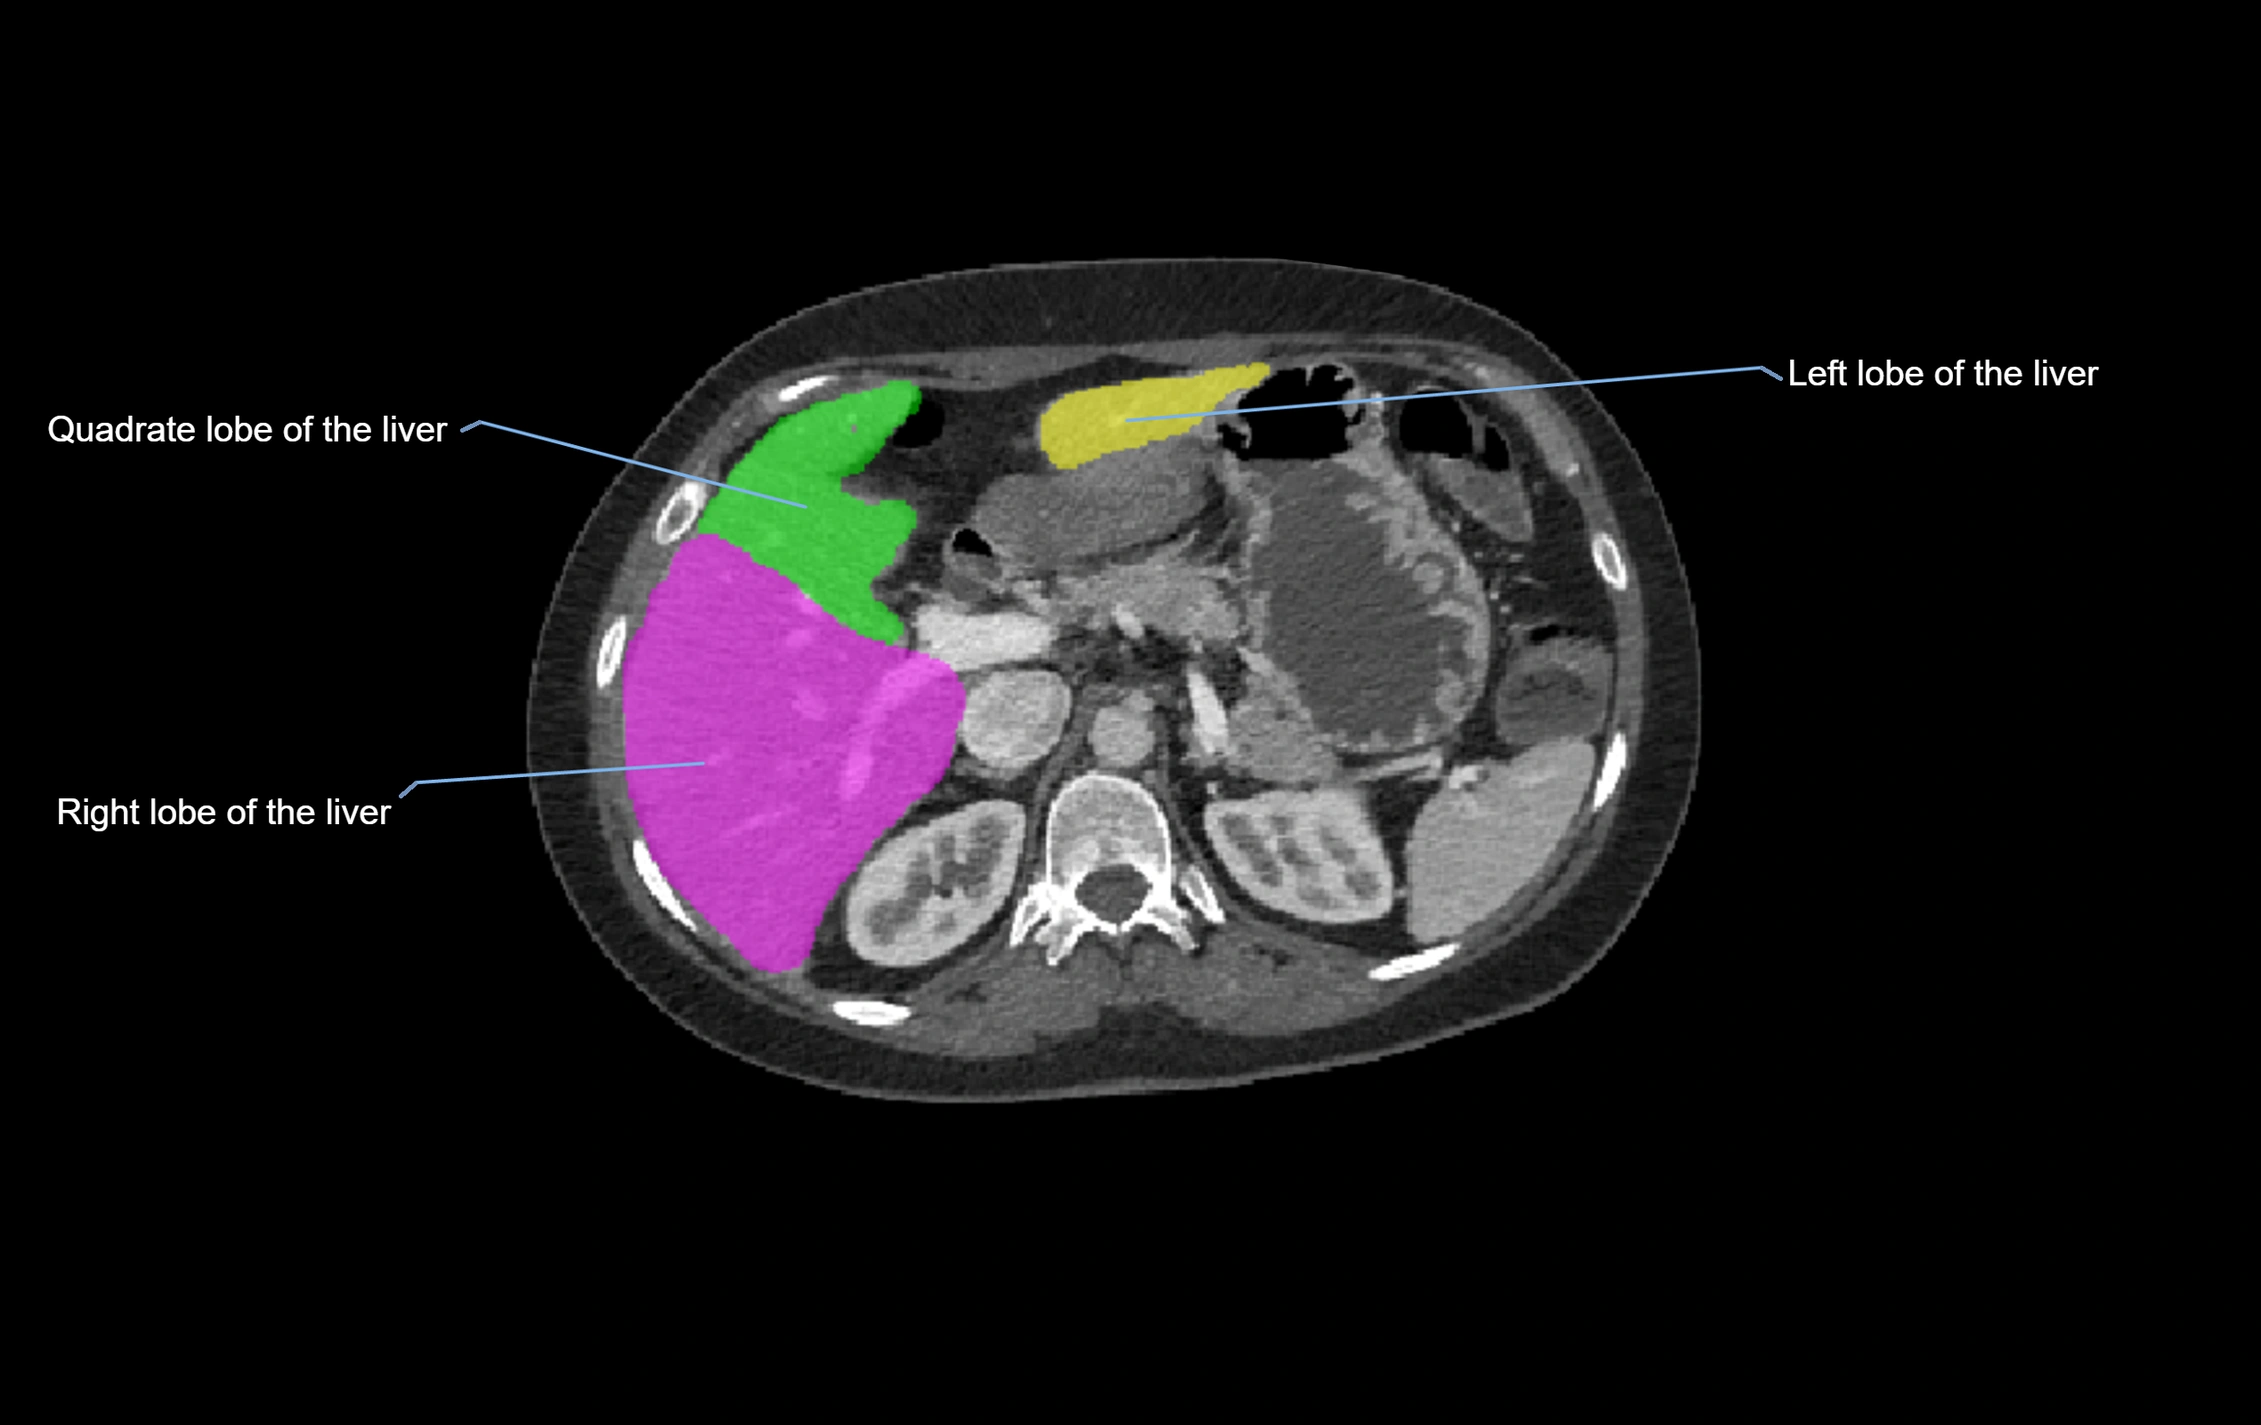

CT Appearance

CT Pre-Contrast:

• Caudate lobe appears as a soft-tissue density, isodense to the rest of the liver

• Enlargement may be appreciated in cirrhosis or Budd–Chiari syndrome

CT Post-Contrast:

• Homogeneous enhancement in the portal venous phase, similar to rest of liver

• Independent venous drainage into the IVC may be visualized

• Lesions follow characteristic CT enhancement patterns (HCC: arterial hyperenhancement with washout; hemangiomas: peripheral nodular enhancement with centripetal fill-in)

CT Venous Phase (functional significance):

• Caudate lobe often enhances relatively more than other lobes in Budd–Chiari syndrome, due to preserved venous outflow